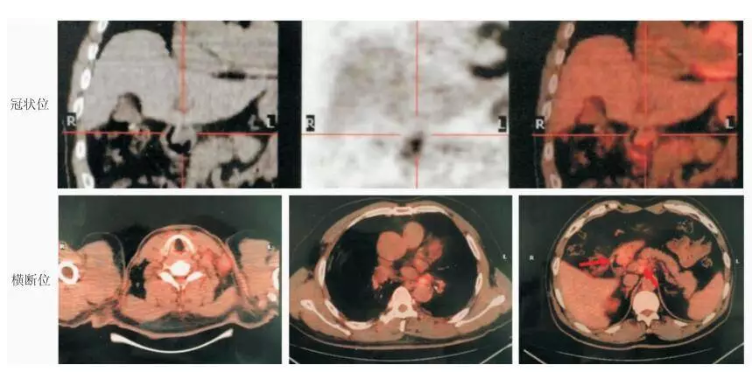

图1. 初诊时全身PET-CT检查结果

图片来源:实用肿瘤杂志2018年第33卷第2期96页